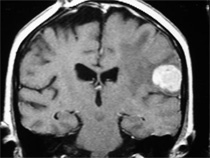

Metástasis Cerebral de cáncer de mama:

Paciente con tumor primario ( CA de mama ) controlado. Hace 1 año metástasis tratadas con radiocirugía en el extranjero. Viene con recurrencia con 2 metástasis. La paciente tiene trastorno del lenguaje (afasia) y parálisis del lado derecho del cuerpo (hemipléjia)

Resonancia magnética al momento de la intervención. Note el gran volumen tumoral y la compresión cerebral.